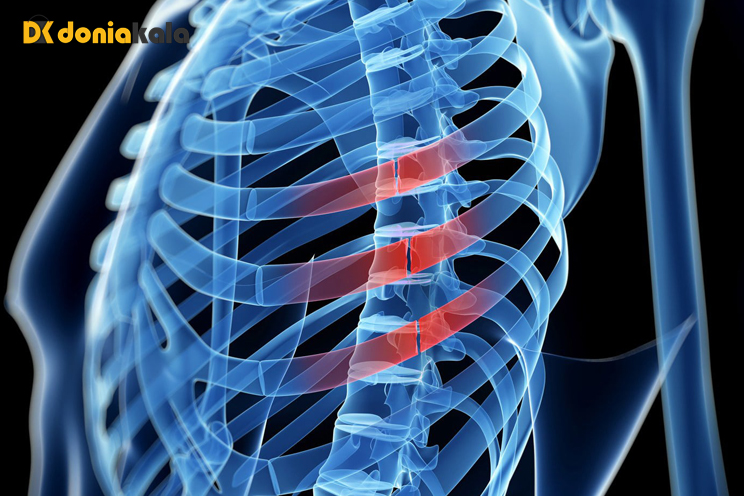

10. شکستگی مهره کمر Lumbar vertebral fracture

غالباً شکستگی مهره در تصادفات، زمین خوردن، تیراندازی یا در هنگام ورزش رخ میدهد. جراحات ممکن است از آسیب دیدگی خفیف رباطها و کشیدگی عضلات تا شکستگی و جابجایی مهرهها و آسیب دیدگی نخاع باشد.